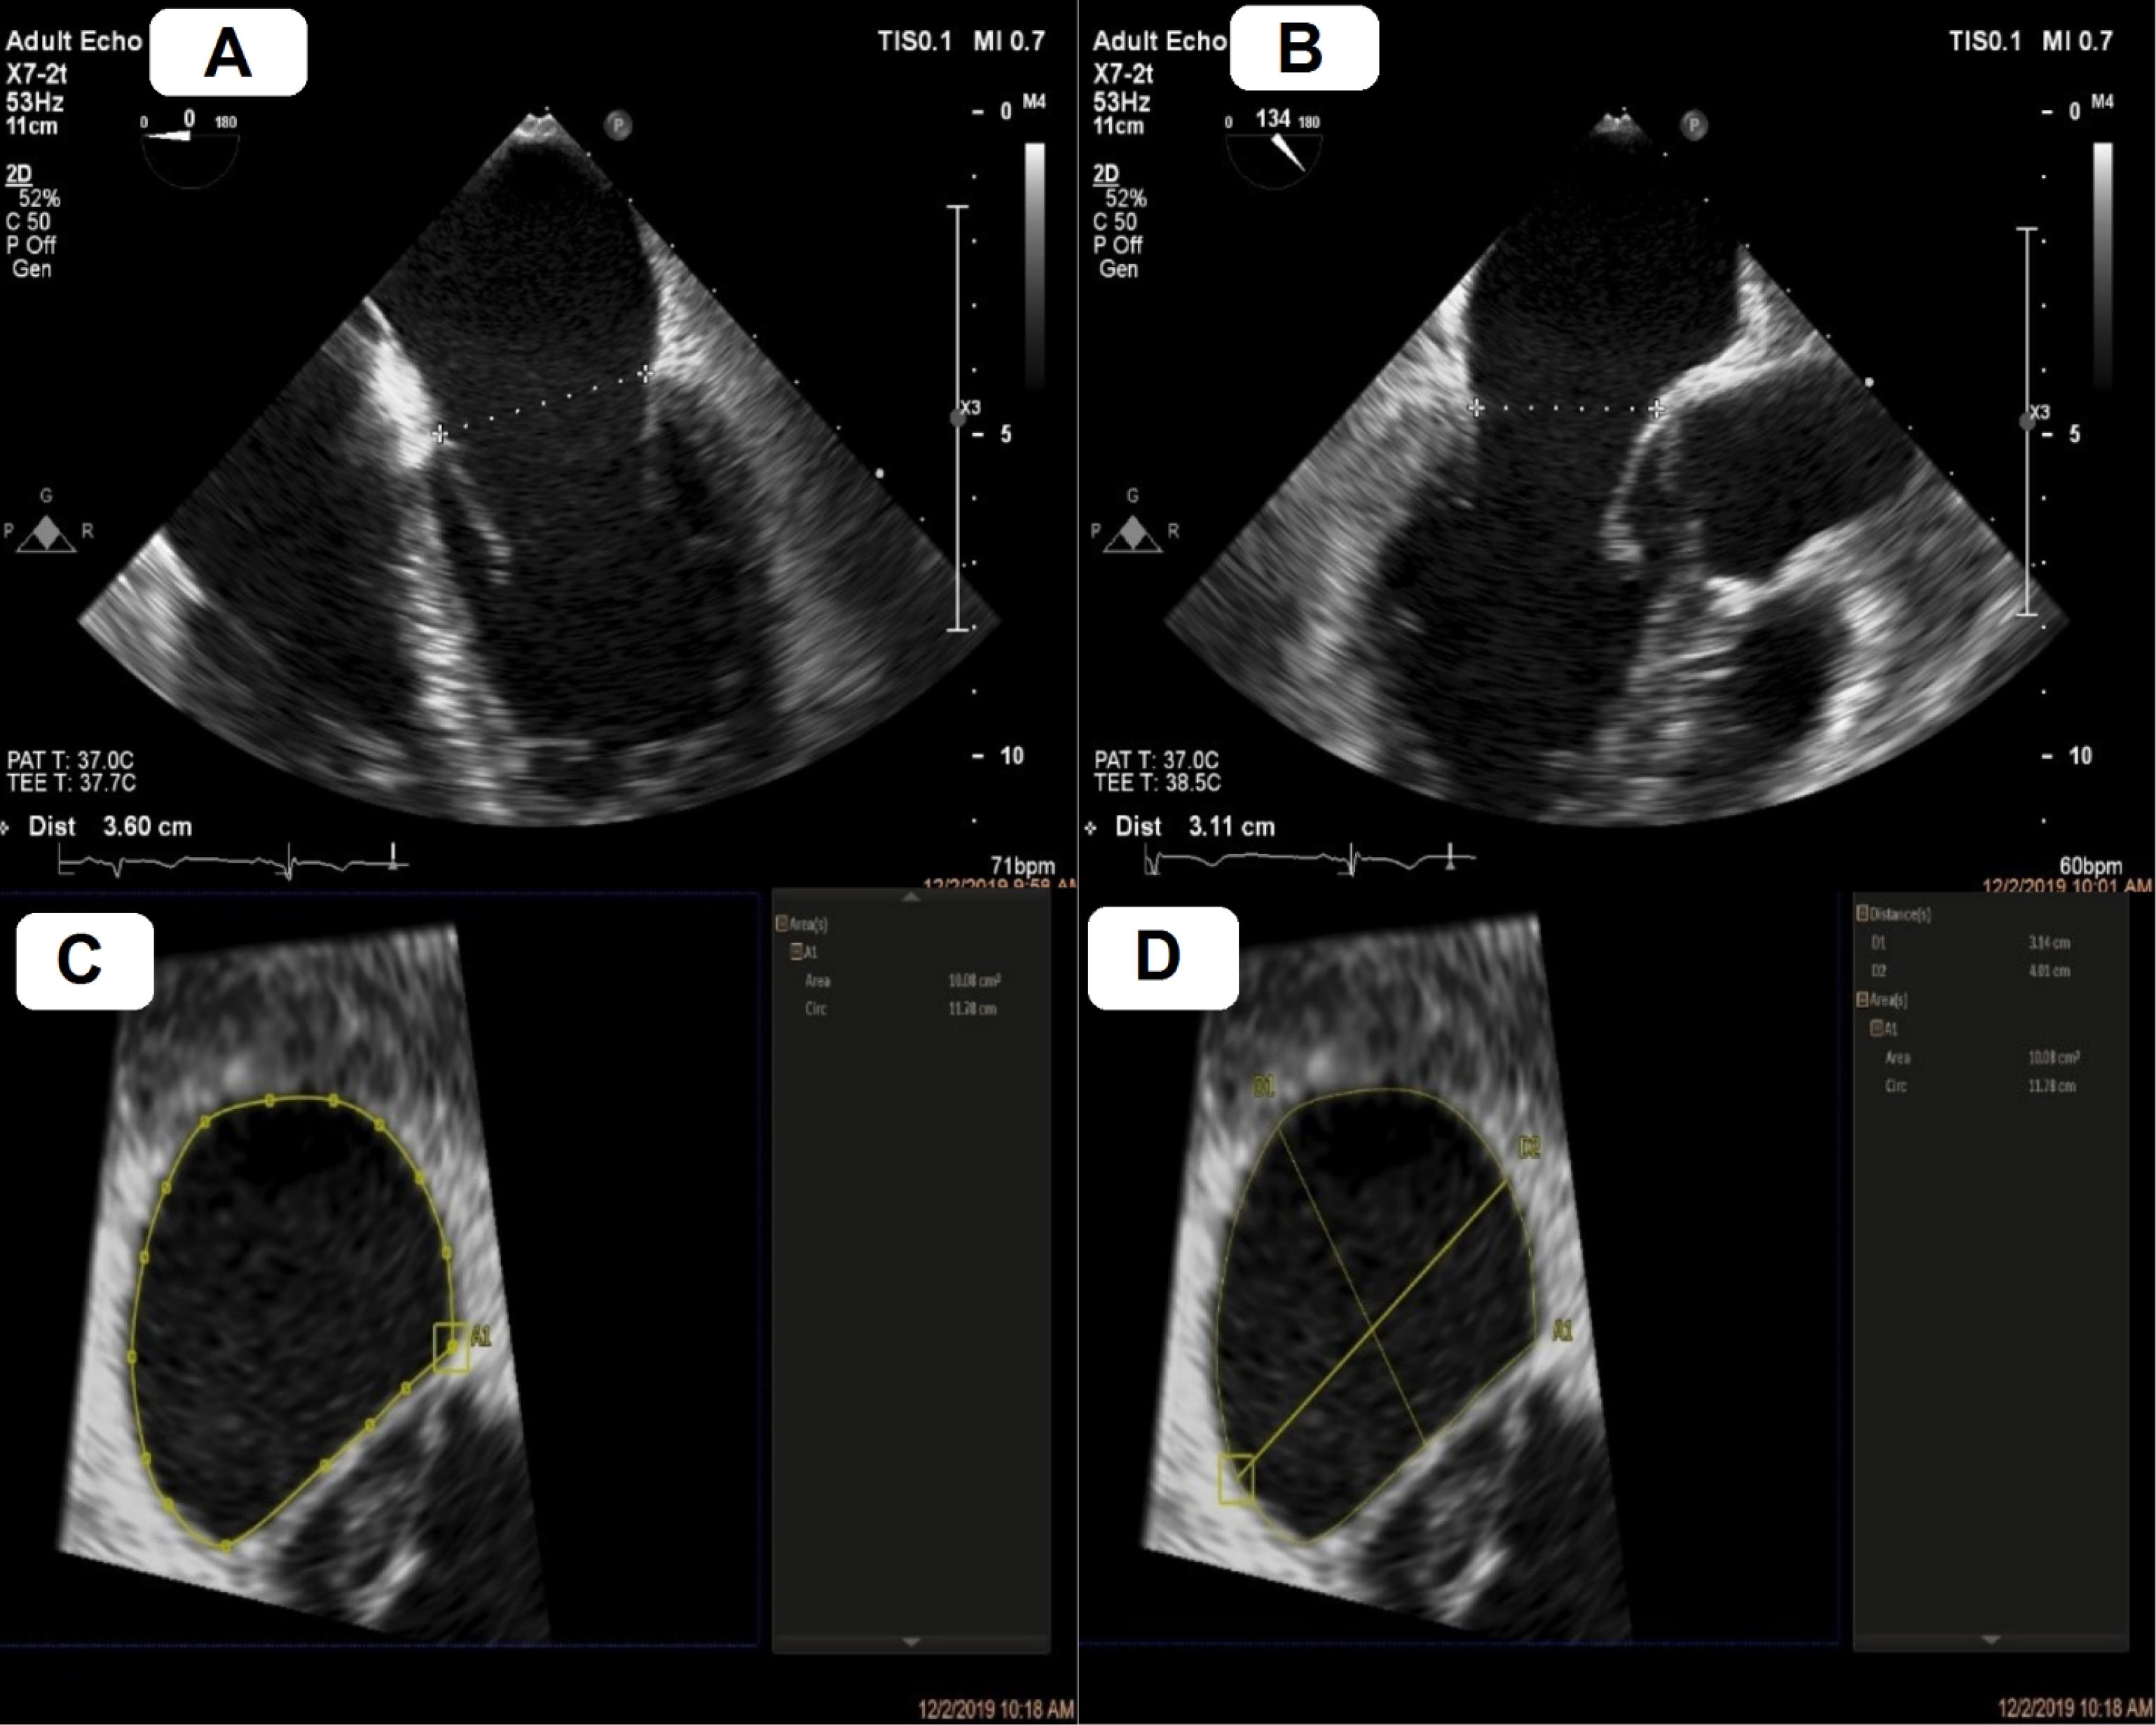

All echocardiographic studies were performed utilizing a Philips® EPIQ 7 ultrasound machine. Mathematical values were calculated using the QLAB software, following the adjustment of the depth and gain of the obtained images (Figure 1). Patients with severe mitral annulus calcification and/or inadequate quality of echocardiographic images were excluded from the study.

Figure 1.

Mitral annulus sizing using two– and three–dimensional transesophageal echocardiography (2D and 3D TEE) software. A, mediolateral annulus by 2D TEE. B, anteroposterior annulus by 2D TEE. C, annulus area and circ by 3D multiplanar reconstruction. D, Long axis (LA) and short axis (SA) by 3D multiplanar reconstruction.